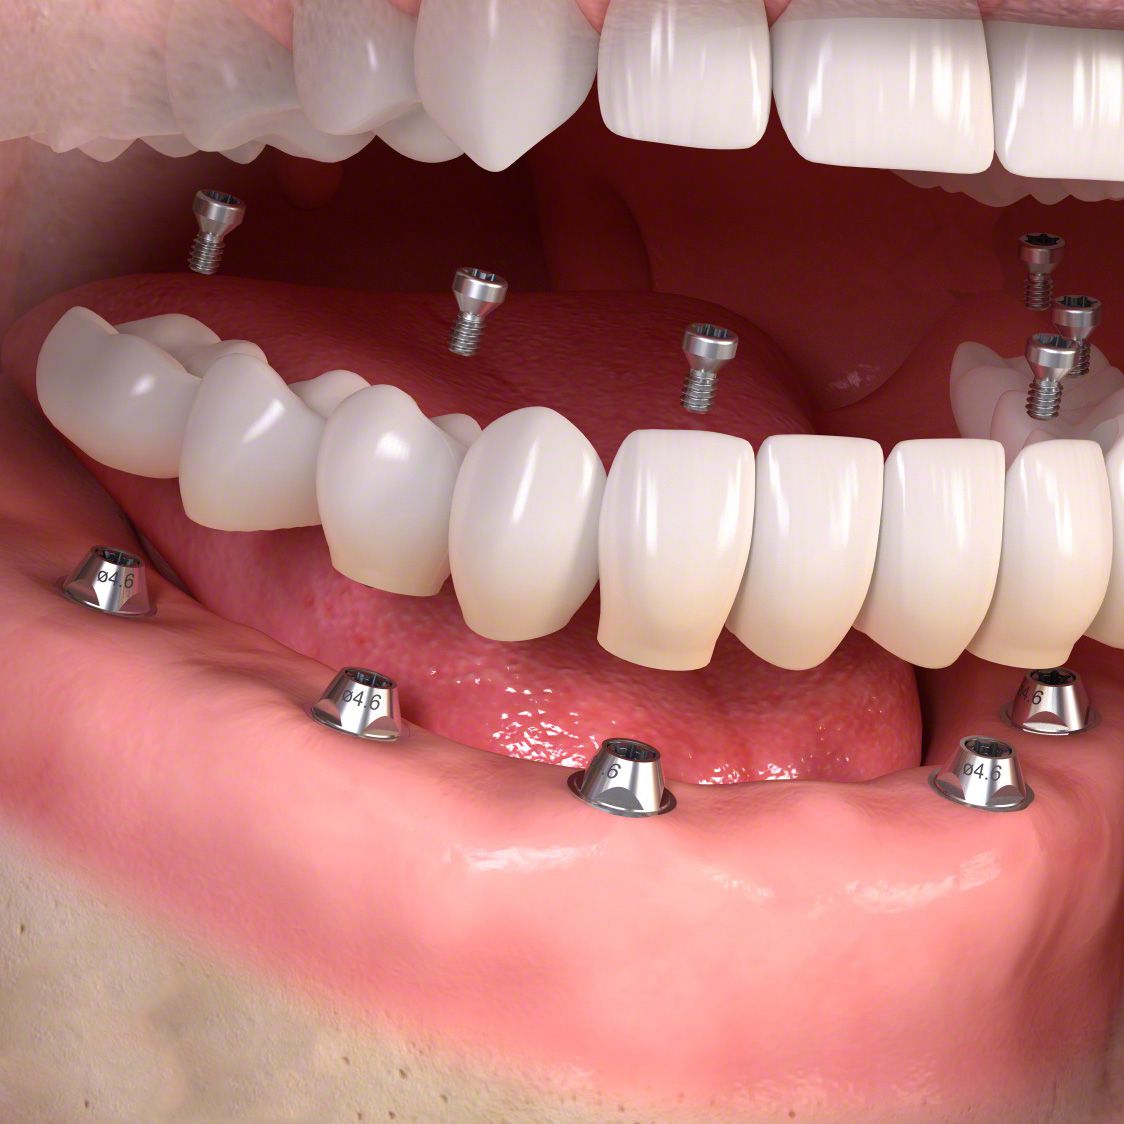

Die entstandene Lücke kann mit einer künstlichen Zahnwurzel, d.h. mit einem Implantat geschlossen werden. Implantate, meist aus Titan oder Keramik, werden dabei in einem kleinen chirurgischen Eingriff in den Kieferknochen eingesetzt. Nach dem Einheilen tragen sie später den eigentlichen Zahnersatz (Kronen, Brücken, Prothesen).

Implantate sind eine langlebige, festsitzende und komfortable Lösung und tragen damit zu mehr Wohlbefinden und Lebensqualität bei. Allerdings brauchen Sie besondere Aufmerksamkeit und Pflege: mit regelmäßiger Prophylaxe – alle 3 bis 4 Monate – werden Sie über viele Jahre Freude an Ihren neuen, festsitzenden Zähnen haben.

Für Implantat-Zahnersatz finden wir in jedem Einzelfall eine passende Lösung. Fragen Sie uns!